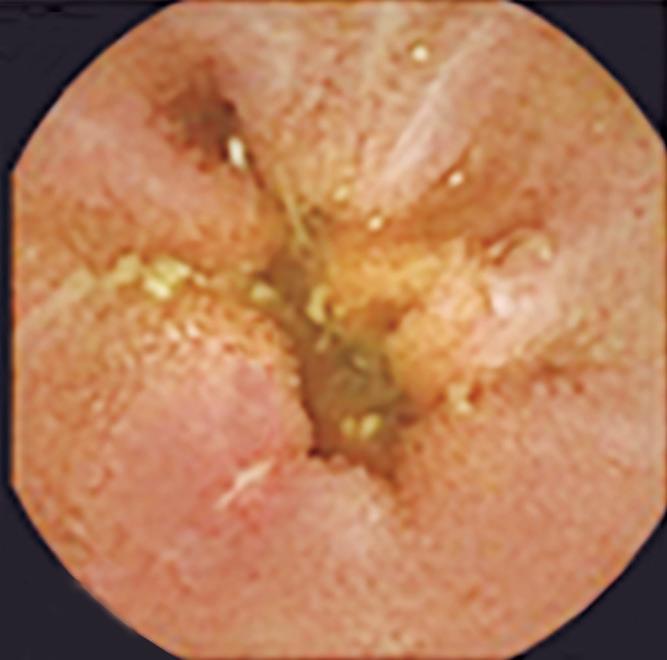

En primer lugar, la endoscopía proporciona información anatómica y mucosa crítica que contextualiza los hallazgos fisiológicos. La graduación de la esofagitis mediante la clasificación de Los Ángeles, la evaluación de EoE con biopsias sistemáticas y puntuación EREFS, la valoración de la válvula gastroesofágica y de la hernia hiatal, así como la identificación de signos endoscópicos sugestivos de acalasia, aportan elementos fundamentales para la interpretación integrada de los datos fisiológicos posteriores.8

En segundo lugar, la introducción de herramientas estructuradas de estratificación endoscópica de riesgo, como el Clinical Achalasia Risk Score (CARS), permite estimar la probabilidad de acalasia basándose en hallazgos endoscópicos reproducibles. El CARS incorpora la evaluación del contenido esofágico, la anatomía luminal, la resistencia a nivel de la UEG y los cambios mucosos relacionados con estasis, demostrando un excelente valor predictivo para acalasia cuando los puntajes superan los umbrales predefinidos.4, 5

Rol del Clinical Achalasia Risk Score (CARS)

Si bien la planimetría FLIP proporciona datos fisiológicos robustos, su poder diagnóstico se ve potenciado cuando se interpreta junto con una estratificación endoscópica del riesgo estructurada. El Clinical Achalasia Risk Score (CARS) fue desarrollado para abordar el retraso diagnóstico persistente asociado a la acalasia, mediante la cuantificación de características endoscópicas vinculadas a la obstrucción del flujo esofágico.9